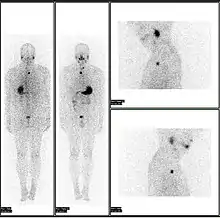

![]() A nuclear medicine PET scan | |

Nuclear medicine or nucleology[1] is a medical specialty involving the application of radioactive substances in the diagnosis and treatment of disease. Nuclear imaging, in a sense, is "radiology done inside out" because it records radiation emitted from within the body rather than radiation that is transmitted through the body from external sources like X-ray generators. In addition, nuclear medicine scans differ from radiology, as the emphasis is not on imaging anatomy, but on the function. For such reason, it is called a physiological imaging modality. Single photon emission computed tomography (SPECT) and positron emission tomography (PET) scans are the two most common imaging modalities in nuclear medicine.[2]